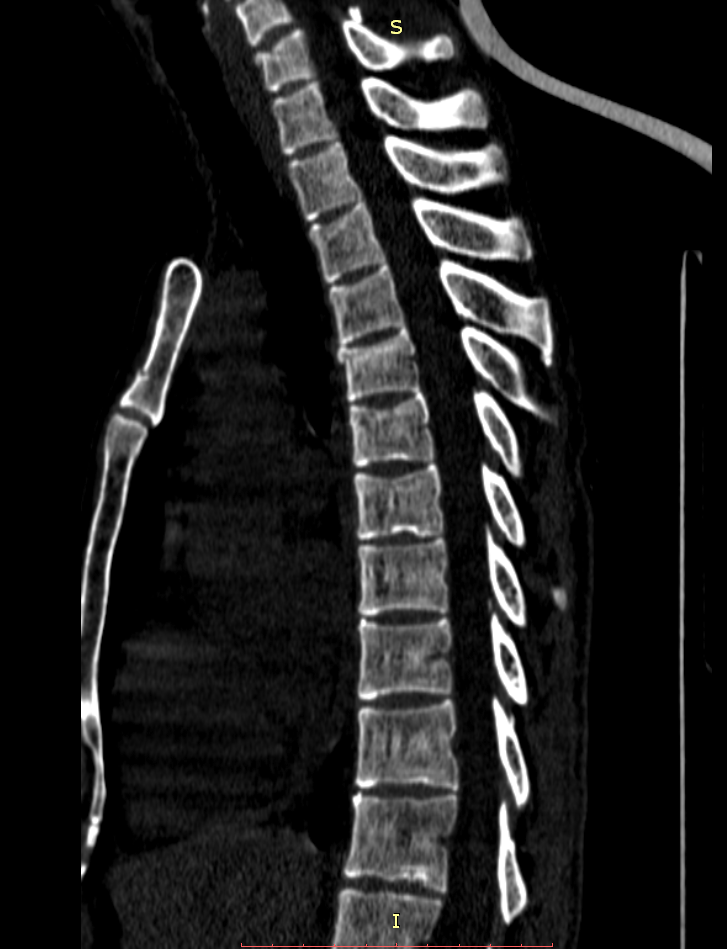

Здравствуйте! Меня сбил автомобиль. Бригада скорой помощи доставила меня в стационар с диагнозом - сотрясение мозга, ушиб грудного отдела позвоночника, компрессионный перелом грудного отдела позвоночника. При поступлении в стационар мне было сделано несколько рентгеновских снимков и поставлен диагноз - компрессионный перелом 4 грудного позвонка. Из-за "мутных" рентгеновских снимков через 9 дней мне сделали КТ и диагноз сняли на основании этого заключения.Судебная медицина - Прикрепленное изображение Мне сказали что перелом шейного позвонка у меня старый и поменяли диагноз - ушиб верхне-грудного отдела позвоночника, болевой синдром. По запросу я получила копию записи КТ. Всю запись КТ выложить не могу, т.к. не могу убрать фамилию. Выкладываю некоторые снимки: Судебная медицина - Прикрепленное изображение Судебная медицина - Прикрепленное изображение Судебная медицина - Прикрепленное изображение Судебная медицина - Прикрепленное изображение Судебная медицина - Прикрепленное изображение Судебная медицина - Прикрепленное изображение Судебная медицина - Прикрепленное изображение Действительно ли по этим снимкам можно сказать, что перелом шейного позвонка "старый"? Правильно ли описание КТ? Я не эксперт, но по-моему 5 грудной позвонок тоже поврежден. Можно ли оспорить заключение врача делавшего КТ? Если можно, то как это сделать? Ведь речь идет об установлении причинно-следственной связи между ДТП и травмой, а до ДТП у меня никаких травм позвоночника не было. Может рентгеновские снимки тоже о чем то скажут.Судебная медицина - Прикрепленное изображениеСудебная медицина - Прикрепленное изображениеСудебная медицина - Прикрепленное изображение

Для этого надо исследовать все сканы. Желательно - с 3D-реформацией изображения. С внимательным анализом костной структуры на уровне дефекта (есть ли признаки отека костной ткани в его зоне, наличие реакции мягких тканей, состояние краев фрагментов и т.д.). Получите все сканы КТ на диске или на флешке (они должны храниться в архиве КТ). И проконсультируйте их у высококвалифицированного специалиста по КТ и/или в любом крупном Бюро судебно-медицинской экспертизе, в штате которого есть эксперт-рентгенолог. Возможно, понадобится сделать контрольное КТ исследование с целью обнаружения динамики выявленных изменений (впрочем, вопрос об этом будет решен после ознакомления рентгенолога с КТ, т.к., возможно, доп.исследование не будет необходимо или же более целесообразным окажется иной вариант лучевой диагностики). По результатам консультации станет понятно, есть ли реальные основания для заявления мотивированного ходатайства о назначении дополнительной или повторной экспертизы (как это сделать - подскажет Ваш адвокат).